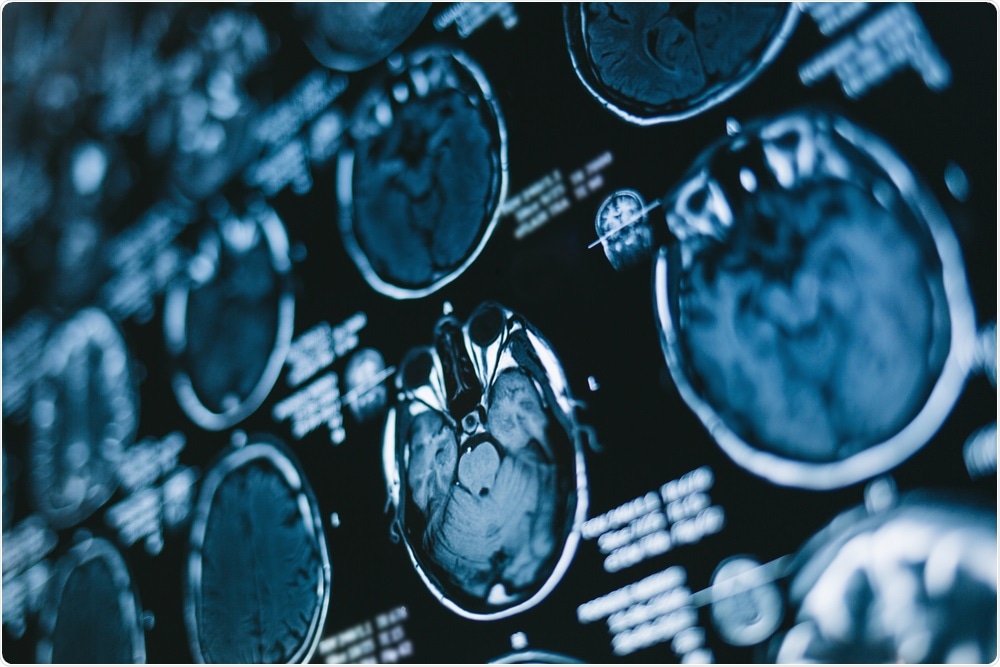

Two dimensional X-ray film of the brainImage Credit: Popartic / Shutterstock